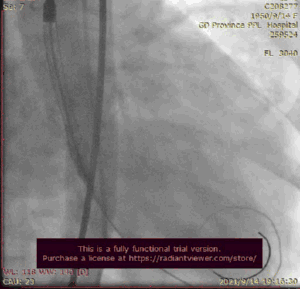

瓣膜定位,降主可见造影剂滞留。